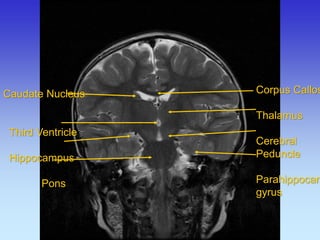

Caudate Nucleus

Third Ventricle

Hippocampus

Pons

Corpus Callosum Thalamus Cerebral Peduncle Parahippocampal gyrus